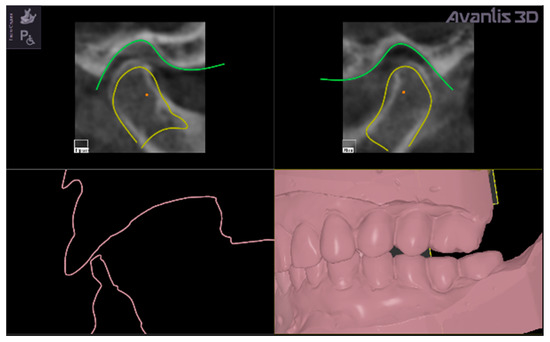

• Matching of .stl files from intra-oral scans of dentition, with CBCT data.

The new occlusal vertical dimension was then established by lower jaw rotation around a virtual hinge axis passing through the middle points of the condyles (Figure 5 evidences two red points that are the middle points of the condyles).

The virtual rotation was established at 0.4 degrees (Figure 4) to obtain the normalization of superior and posterior space widths.

The middle points of the condyles (represented as red points in Figure 5) are determined automatically by the software on the CBCT 3D reconstruction, connecting the right and left poles of each condyle, thus individuating the middle point of the major condylar axes.

The virtual setting of the lower jaw position allowed to obtain a symmetrical repositioning of the two condyles in the glenoid fossa, with the width of the intra-articular spaces never going below the normal range of values. (Figure 4 and Figure 5)

Figure 5. Representation of the virtual shifting of the condyles to normalize the values of the intra-articular space width (yellow contours) and degrees of rotation around intercondylar axis (the virtual hinge axis is the line passing through the red points in condylar heads) to establish the new vertical occlusal dimension (evidenced by pink contour) that is represented as a gap between upper and lower digital models, which will be filled by the virtually designed intra-oral repositioning splint.